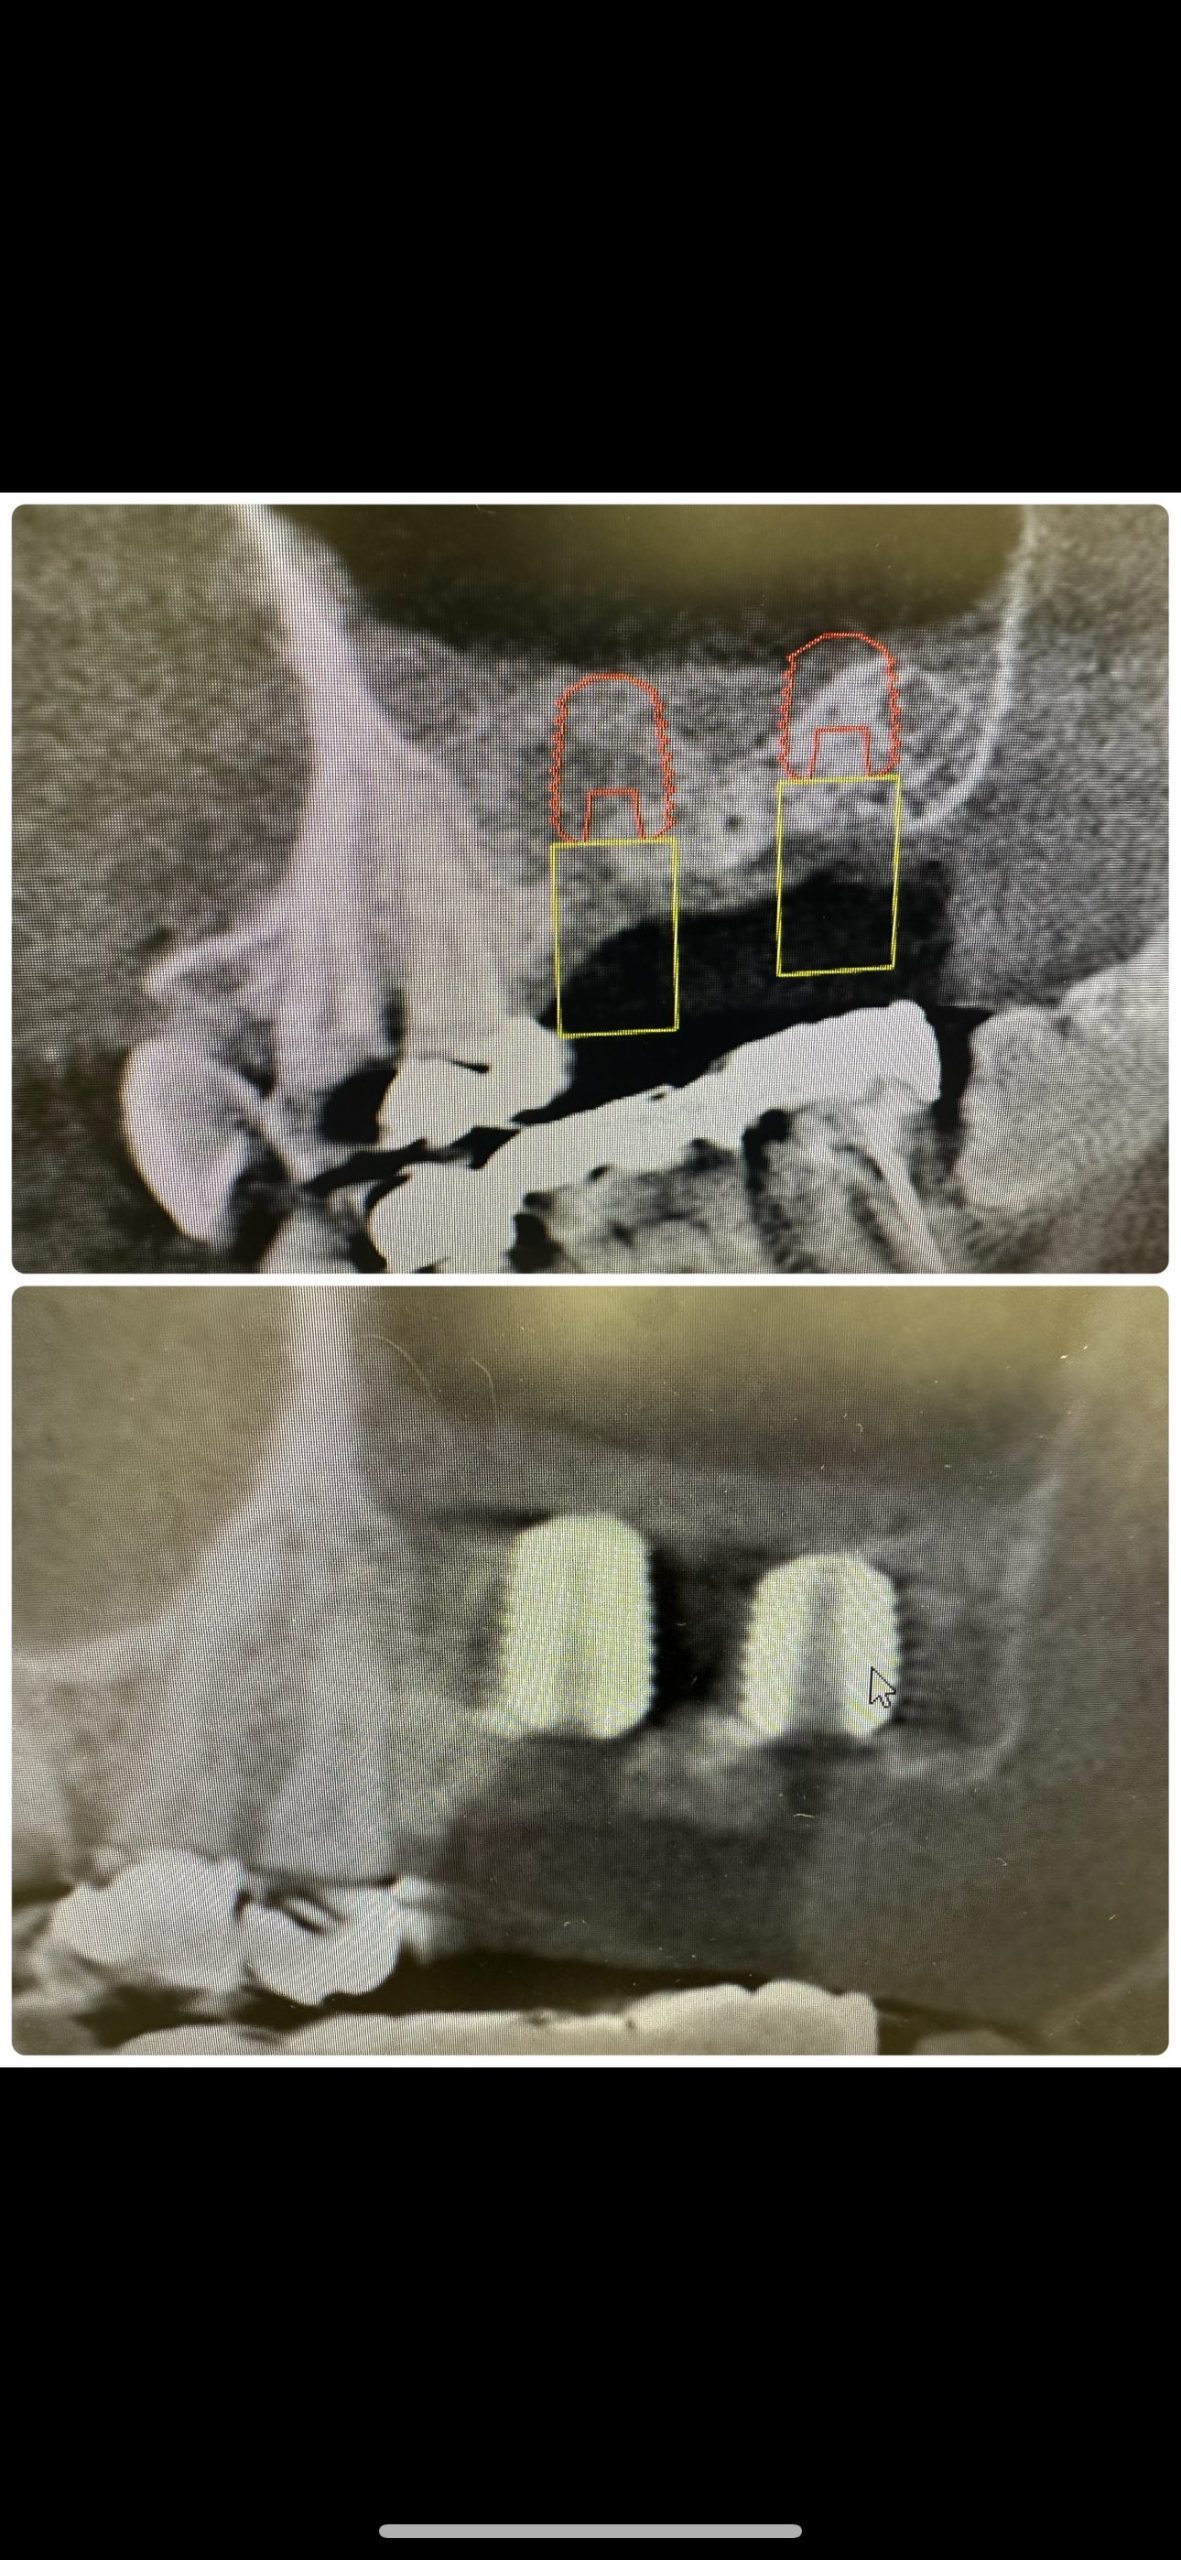

もう駄目かなあ?と考えていたが、自然治癒力は素晴らしい

愛用している、特級水酸化カルシウム、カルビタール

症例に応じて使い分け

メーカー発売製品は効能が乏しい、元昭和大学歯学部歯内療法科松本光吉教授の教え!🤪

興地論文

特級が1番ですよ‼️

貼薬剤だけでは駄目、他諸々技術あり、それは秘密㊙️🤫